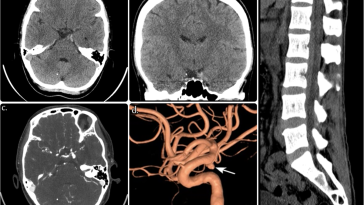

Revolutionizing Craniocervical Dural Imaging with Endoscope Integrated Indocyanine Green Videoangiography

Understanding the Challenges of Craniocervical Vascular Malformations In recent years, the management of vascular malformations at the craniocervical junction has been on the forefront of neurosurgical innovation. This editorial takes a closer look at the evolving techniques that combine advanced imaging technology with minimally invasive procedures, focusing on the role of endoscope‐integrated indocyanine green (ICG) […] More